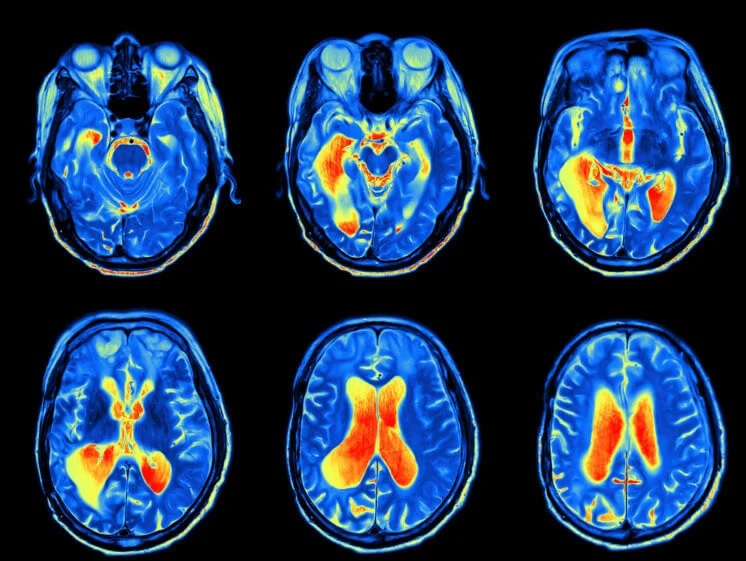

Коронавирус способен проникать в мозг

В подавляющем большинстве случаев CоVID-19 протекает как респираторная инфекция, которая вызывает лихорадку, усталость, боль в горле, кашель и, в более тяжелых случаях, одышку и затруднение дыхания. Однако результаты последних научных исследований показали, что вирус SARS-CoV-2, предположительно, уже мутировал в 30 различных штаммов, а многие инфицированные не испытывают никаких симптомов, но при этом остаются заразными. Еще более тревожно выглядят данные о том, что более чем у трети пациентов наблюдаются неврологические симптомы, такие как тяжелый энцефалит, который вызывает воспаление и отек мозга.

В других случаях исследования описывали тяжелый энцефалит у больного CоVID-19 (воспаление и отек головного мозга) и инсульт у здоровых молодых людей с легкими симптомами CоVID-19. На эту особенность нового коронавируса обратили внимание ученые из Китая и Франции и исследовали распространенность неврологических расстройств у пациентов CоVID-19. Полученные результаты показали, что 36% пациентов имеют неврологические симптомы. Многие из этих симптомов были легкими и проявлялись головной болью или головокружением, которые могли быть вызваны сильным иммунным ответом организма. Но также были замечены и другие более специфические и тяжелые симптомы, включающие потерю обоняния или вкуса, мышечную слабость, инсульт, судороги и галлюцинации.

Отек и повреждение мозга

SARS-CoV-2, как полагают специалисты, может стать причиной появления неврологических расстройств. Это происходит либо непосредственно из-за заражения мозга, либо в результате чрезмерной реакции иммунной системы на коронавирус. Так, последние исследования смертельных случаев CoVID-19 выявили новый коронавирус в головном мозге зараженных. Также было высказано предположение о том, что инфекция обонятельных нейронов в носу может способствовать распространению вируса из дыхательных путей в головной мозг.

Клетки человеческого мозга экспрессируют белок ACE2 на своей поверхности. ACE2 – это белок, который участвует в регуляции кровяного давления и является рецептором, который вирус использует для проникновения и заражения клеток. Этот белок обнаружили на клетках эндотелия, выстилающих кровеносные сосуды и отвечающих за множество функций сосудистой системы. Зараженные клетки эндотелия могут позволить вирусу пройти из дыхательных путей в кровь, а затем в мозг, где размножение вирусных частиц может стать причиной появления неврологических симптомов.